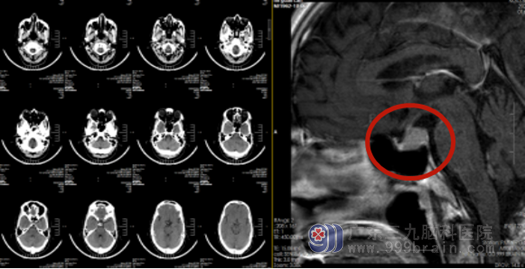

影像检查:

术后MR